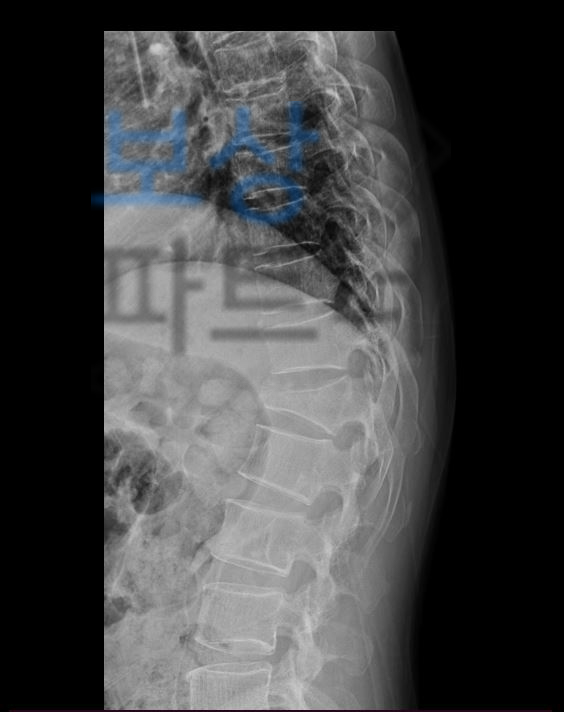

한@@님은 즉시 응급실로 내원하여 엑스선 검사를 물론이고 Mri , CT 검사등 정밀검사를 받으셨는데요,

흉추, 요추 후방 유합술 (고정술) 산재 장애등급 7급 손해보험 보상 심각한 척추 골절로 안정성 확보를 위해 흉추10번 부터 요추2번 까지 후방 유합술 즉 수술적 치료를 받으셨습니다.

Spinal fixation of T10~L2